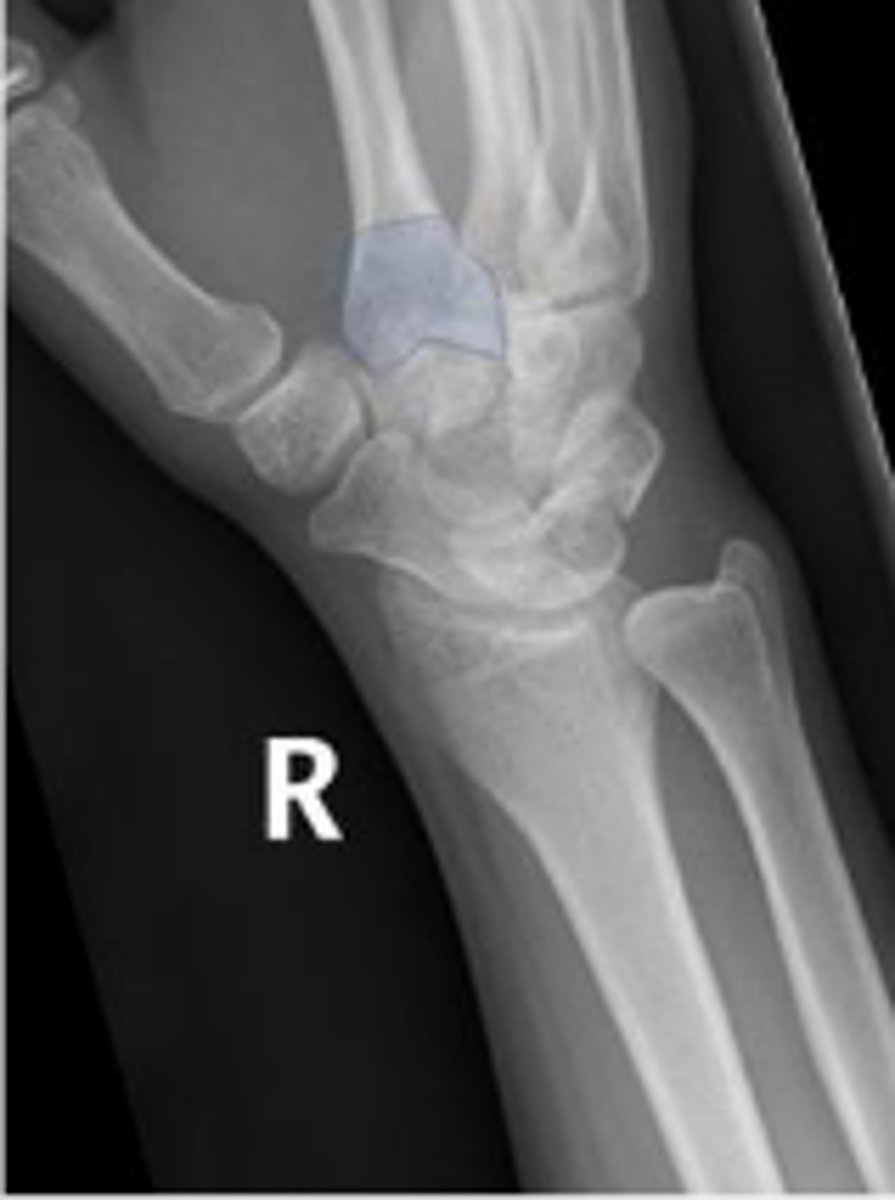

Right lunate

What is outlined?